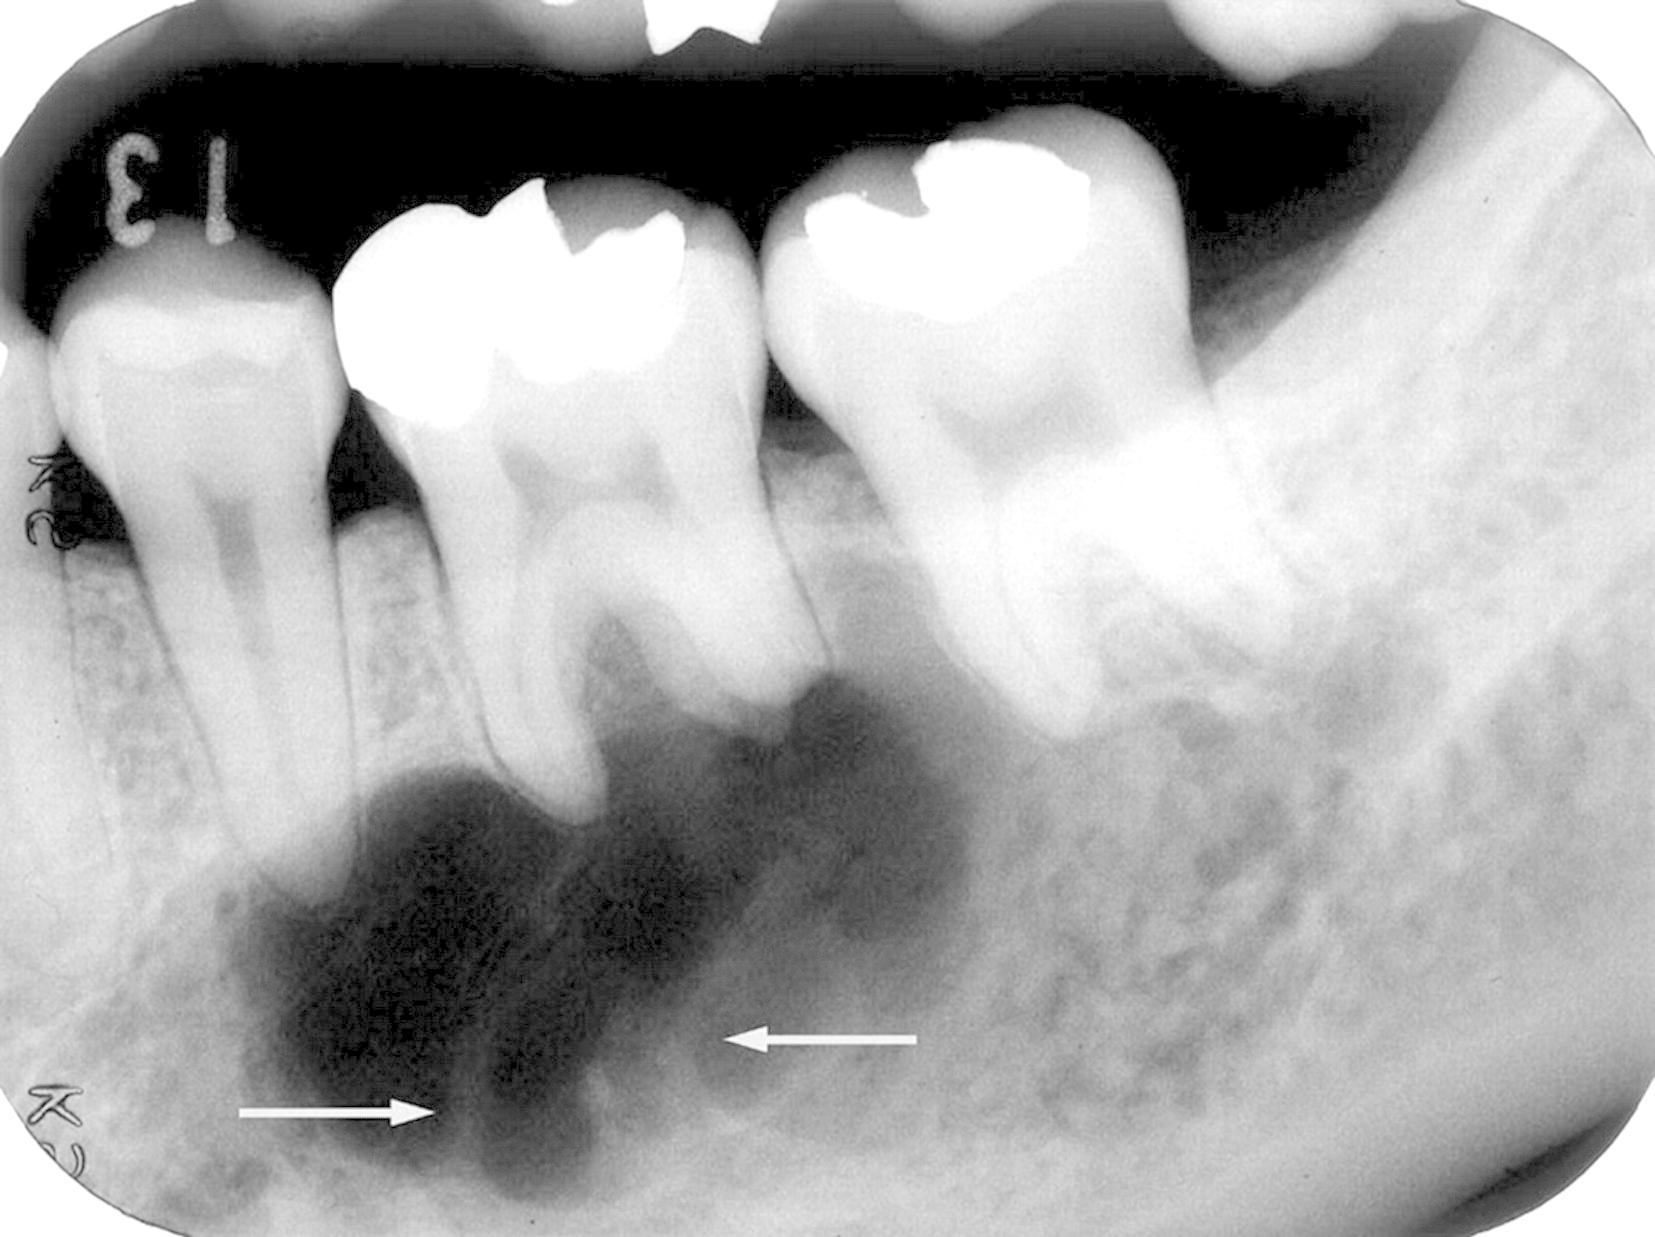

Анатомия: Межкорневая костная перегородка

Раздел: Галерея впечатлений